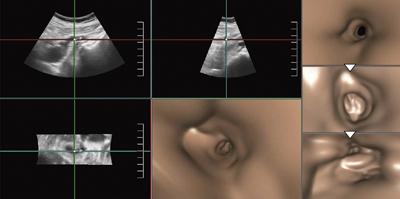

Fly Thruでは,プローブで取得した超音波データから透視投影像を再構成することで,管腔内や血管内を立体的に移動する画像が得られる。X線CTのデータを再構成した仮想内視鏡と同様の画像で,管腔や血管内を“飛ぶ(Fly Thru)”ことができるアプリケーションである。超音波の画像データでは,細径血管の描出は難しいが,これまで当院で経験した症例の画像を提示する。

膵頭部がんによる閉塞性黄疸の症例(図2)では,膵頭部がんが大きいためERCPの挿管が困難で画像が得られなかったが,体表からの超音波によってFly Thruの3D画像を作成した。肝門部から乳頭側へ胆管内を視点移動し,狭窄,閉塞の状況が観察できたほか,胆管の表面性状は比較的平滑であることもわかった。

図2 膵頭部がんによる閉塞性黄疸のFly Thru画像

(肝門部→乳頭側へ)

ERCPにおける挿管困難例でも管腔の情報が得られる。

肝門部胆管がんの症例(図3)では,肝内胆管が拡張して肝門部に腫瘍がある。3D画像で胆管内を末梢から腫瘍に向かって視点移動することで,門脈浸潤の有無や,圧排か浸潤かなどの胆管と腫瘍との関係を,MPR画像と対比して観察することができた。

図4は,胆管がんのステント留置症例だが,Fly Thruでは留置されたダブルピッグテイルステントの形状を認識できる精度がある。視点は,末梢からステントへ移動するが,ピッグテイルステントの先端の輪の部分を観察できる。

図3 肝門部胆管がんのFly Thru画像(末梢胆管→腫瘍へ)

個々の胆管や門脈と腫瘍との関係をMPR画像との対比で

より把握しやすい。

図4 胆管がんステント留置症例のFly Thru画像 (ステントをくぐり末梢へ) (動画)

MPR画像と対比することで病変のより詳細な評価が可能になる

Fly Thruの利点としては,1つは超音波に馴染みのない医療従事者や患者にとって,わかりやすい表示であることである。超音波のトレーニングを受けていれば,頭の中で2D画像から立体的な構造を再構成することは容易だが,Fly Thruは,管腔の変化をより客観的に正確に把握できる手法である。さらに,MPR画像との対比で,内腔の状態や腫瘍浸潤の様子などを詳細に評価することが可能になる。